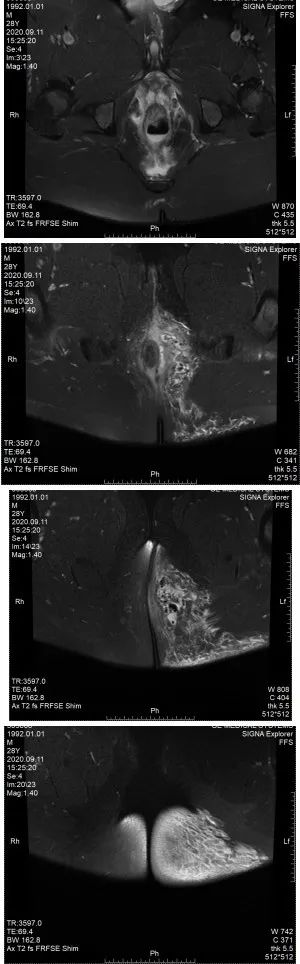

肛肠科主任医师再次查看病人,此时肛周MRI结果回示:直肠周围及左臀部、会阴部异常信号,考虑肛周脓肿并周围软组织水肿,建议增强扫描检查。图附下。

可见气液平面及组织间隙气体

白细胞及c反应蛋白均较前增高,且白细胞超过20×10^9/L,出现低蛋白血症,血红蛋白降低(贫血征兆),出现低钠、低钙电解质紊乱。感染较前次增加,提示重度感染,查看患者臀部红肿范围,1点位肿块红肿更加明显,范围较前增大,左侧臀部红肿范围亦有向后背部扩展迹象。结合肛周MRI,左侧臀部及会阴部皮下脂肪间隙模糊,见片状长T1长T2信号影,边缘不清,局部见斑片状气体密度影。主任医师查看病人后考虑:患者有坏死性筋膜炎可能,应立即行手术治疗,避免感染性休克及炎症的快速扩散导致生命危险。